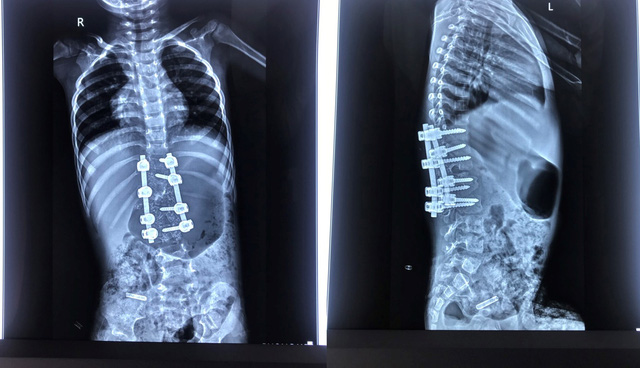

Hình ảnh phim chụp cột sống bệnh nhi B.Đ sau khi mổ, đã được nắn chỉnh vẹo cột sống.

Về mặt phẫu thuật, bé Đ. còn nhỏ tuổi nhưng đã biến dạng cột sống rất lớn, có dị tật nửa thân đốt L1 bên phải, thiểu sản cuống sống T12 bên phải. Do vậy, tính chất cuộc phẫu thuật rất phức tạp. Bé có nguy cơ mất máu lớn, tổn thương tủy và không có loại vít cột sống nào dành cho bé. Bên cạnh đó, gây mê cho trẻ 3 tuổi, nặng chỉ 12 kg cũng là thách thức với ê-kíp.Nhờ sự phối hợp chặt chẽ, ca phẫu thuật diễn ra gần 4 tiếng đã thành công. Sau mổ, bệnh nhi đã được nắn chỉnh tốt biến dạng cong vẹo cột sống, không có tổn thương thần kinh. Bệnh nhi hồi phục thuận lợi, hai chân vận động bình thường. Bệnh nhi đang tập ngồi và đi lại được, tiểu tự chủ. Hình ảnh X-quang sau mổ cho thấy biến dạng được nắn chỉnh rất tốt, còn giữ được chức năng 3 đĩa đệm cuối cùng của cột sống thắt lưng.Mẹ bệnh nhi B.Đ chia sẻ: "Sau khi gia đình phát hiện ra căn bệnh của cháu. Mặc dù đã đưa đến một số bệnh viện nhưng không thể tiến hành phẫu thuật. Qua thông tin trên truyền hình, gia đình biết đến Bệnh viện TWQĐ 108 đã có những ca thành công với căn bệnh này nên chúng tôi đã quyết định cho cháu đến đây chữa bệnh. Quả thật, khi tiếp xúc và chứng kiến tấm chân tình của các bác sĩ nơi đây, tôi vô cùng xúc động…"